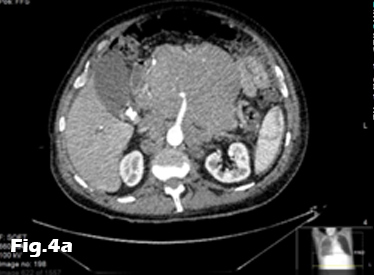

We present the case of a 59-year-old male, previously fit and well who presented to the General Practitioner with a 3 week history of epigastric pain, shortness of breath and unintentional weight loss. On examination, there was evidence of abdominal distension and palpable swelling of left testes. Initial investigation with US of the scrotum revealed dilated (maximally 5.3mm) left pampiniform plexus with retrograde flow on Doppler ultrasound and Valsalva manoeuvre, consistent with an extensive unilateral varicocele (Fig. 1 and 2). Subsequent abdominal ultrasound demonstrated moderate ascites, dilated common bile duct, large right sided pleural effusion and a large 14x14cm solid, vascular epigastric mass. This prompted urgent surgical referral and further cross-sectional imaging (Fig. 3). CT abdomen showed a large soft tissue density retro-peritoneal mass obliterating the portal mesenteric vein circulation and causing the left varicosity (Fig. 4). Ultrasound guided biopsy of the central abdominal mass confirmed a Stage IV Mantle cell Lymphoma.

Figure 1:Scrotal ultrasound showing left sided varicocele.